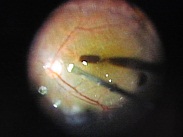

写真だと水色の部分が視神経乳頭(マ盲点)になります。ちなみに、物を見る中心部の網膜は黄斑と呼ばれ、オレンジの矢印に当たります。